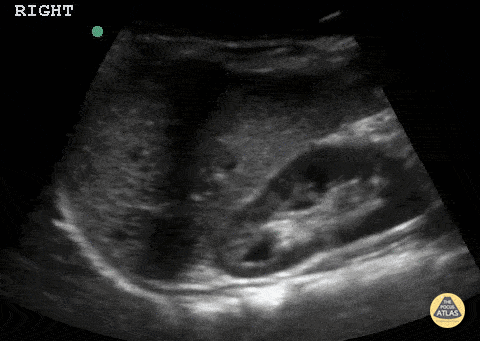

2 year female with history of febrile UTI. Normal right kidney. Note the hypoechoic renal pyramids, which can be misinterpreted as being hydronephrosis. Contributor: Matthew Moake, MD PhD